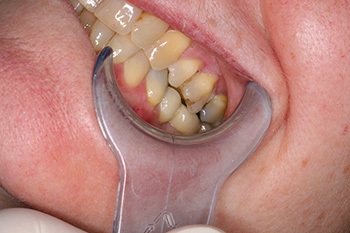

Fig. 1: Pre-op with missing molar.

Fig. 2: Pre-op occlusion.